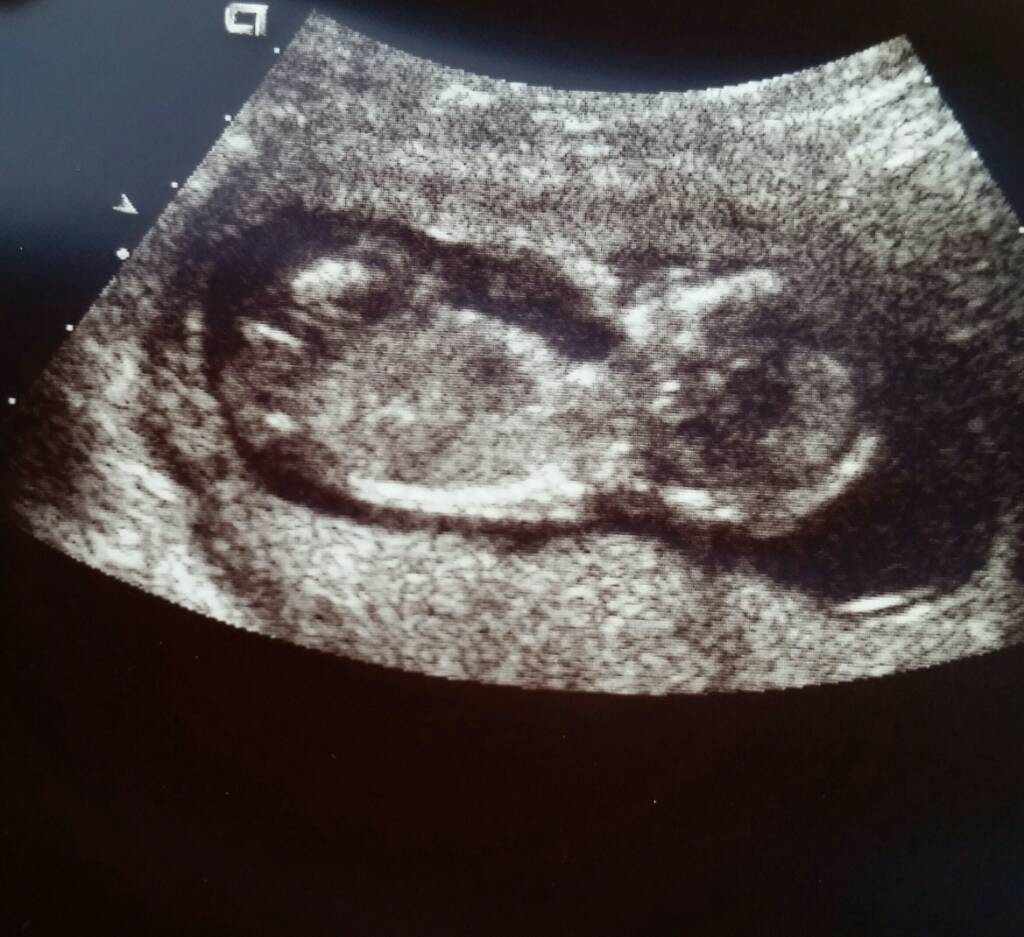

Does this look like a boy nub or girl nub to you? I was told girl once, but I wanted to get more opinions. Thank you.Attachment 34171